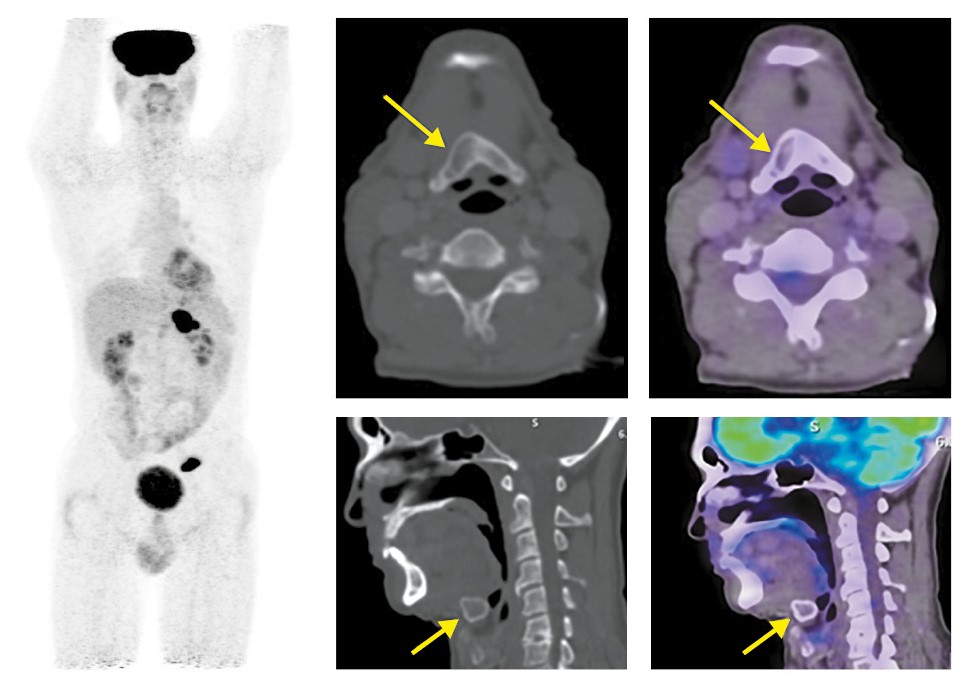

Отмечается вздутие подъязычной кости на всем протяжении с фрагментарной литической деструкцией кортикального слоя (SUVmax 11,9); рис. 3.

Рис. 3. Пациент Т., 54 года. На MIP и аксиальных КТ- и ПЭТ/КТ-проекциях отмечается вздутие подъязычной кости на всем ее протяжении с фрагментарной деструкцией кортикального слоя и диффузно повышенной метаболической активностью 18F-ФДГ, SUVmax 11,9 (стрелки).

Установлен диагноз: рак желудка стадии IV cT4bN3аM1, метастазы в подъязычную кость, л/у средостения, забрюшинные л/у.